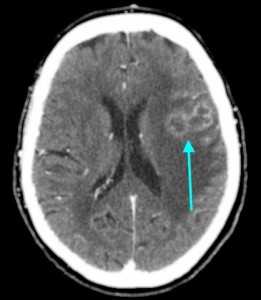

МРТ-признаки метастазов в мозг

МРТ — более чувствительный и специфичный метод в выявлении метастазов ЦНС по сравнению с компьютерной томографией. Вторичные опухоли имеют ряд общих черт при МР-исследовании.

Т1 ВИ (без контрастного усиления)

- Изоинтенсивный либо умеренно гипоинтенсивный сигнал по отношению к белому веществу мозга от активной части опухоли

- Гипоинтенсивный сигнал от центральной зоны (некроза и распада)

Т2 ВИ

- Гиперинтенсивный сигнал от центрального участка метастаза

- Повышение интенсивности сигнала от отечных тканей мозга, окружающих вторичную опухоль, вследствие чего метастазы становятся более четкими на изображениях

МРТ с контрастным усилением

- Выраженное увеличение интенсивности сигнала

- Усиление сигнала по периферии в виде «кольца» или «короны»

- Помогает дифференцировать кровоизлияиния в метастаз от геморрагического инсульта (выраженное усиление сигнала на Т1 ВИ)

Метастазы головного мозга на МРТ. Фото. Определяются множественные метастазы в мозг при раке легкого: слева в режиме Т1-ВИ в виде гипоинтенсивных образований, справа — в режиме Т2-ВИ виде множественных участков повышенного сигнала, окруженных зоной перифокального отека. У пациента подтверждена первичная опухоль легкого.